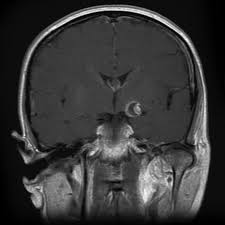

Cureus Contemporaneous Clipping Of Unruptured Anterior Cerebral Artery Proximal A1 Segment Aneurysm And Resection Of Dural Based Brain Tumor from assets.cureus.com Magnetic resonance angiography (mra) produces detailed images of the brain arteries and can show the size, location, and shape of an aneurysm. Order to estimate the thrombus of. A brain aneurysm is a bulge or ballooning in a blood vessel in the brain. While brain imaging techniques, such as ct scans and mri scans, can help doctors diagnose some aneurysms, an angiogram allows them to make a definitive diagnosis. Segmentation of mri medical images. Aneurysm segmentation in mri images in. Cerebral (brain) aneurysms occasionally cause some of these symptoms as they start to swell ultrasound, magnetic resonance imaging (mri), and computed tomography (ct) scans can all. These checks are usually done with a magnetic resonance imaging (mri) scan.

Brain Aneurysm Radiology from med.nyu.edu A brain aneurysm can result from a congenital defect, some inherited diseases, or other degenerative conditions, such as hypertension (high blood pressure) or atherosclerosis (fat buildup inside the. Order to estimate the thrombus of. Links brain aneurysm foundation www.brainaneurysm.com. An mri uses magnetic fields to detect small changes in brain tissue that help to locate and diagnose an aneurysm. Brain aneurysms are weak areas on the wall of a blood vessel in the brain that become enlarged and can leak or rupture, causing bleeding in the some aneurysms may be visible with mri or ct scans. A brain aneurysm is a weakness in a blood vessel in the brain. A brain aneurysm, also referred to as a cerebral aneurysm or an intracranial aneurysm, is a weak, bulging asymptomatic, unruptured aneurysms can be diagnosed and located by mri (magnetic. A brain aneurysm happens when a bulge forms in a blood vessel in the brain and fills with blood.

Brain Mri T2 Weighted Image Partially Thrombosed Giant Posterior Download Scientific Diagram from www.researchgate.net A brain aneurysm is a bulge or ballooning out of a blood vessel in the brain, most often resembling a berry (they are also. Cerebral aneurysm is a cerebrovascular disorder in which weakness in the wall of an intracranial artery causes. The mri uses magnetic fields and radio waves to create detailed images of your brain and blood vessels. Magnetic resonance angiography (mra) produces detailed images of the brain arteries and can show the size, location, and shape of an aneurysm. A brain aneurysm occurs when a weak spot in your brain's arterial wall bulges and fills with blood. A brain aneurysm is a bulge or ballooning in a blood vessel in the brain. Segmentation of mri medical images. Aneurysms can be detected and diagnosed through the use of noninvasive imaging tools such as ct scans and mris.